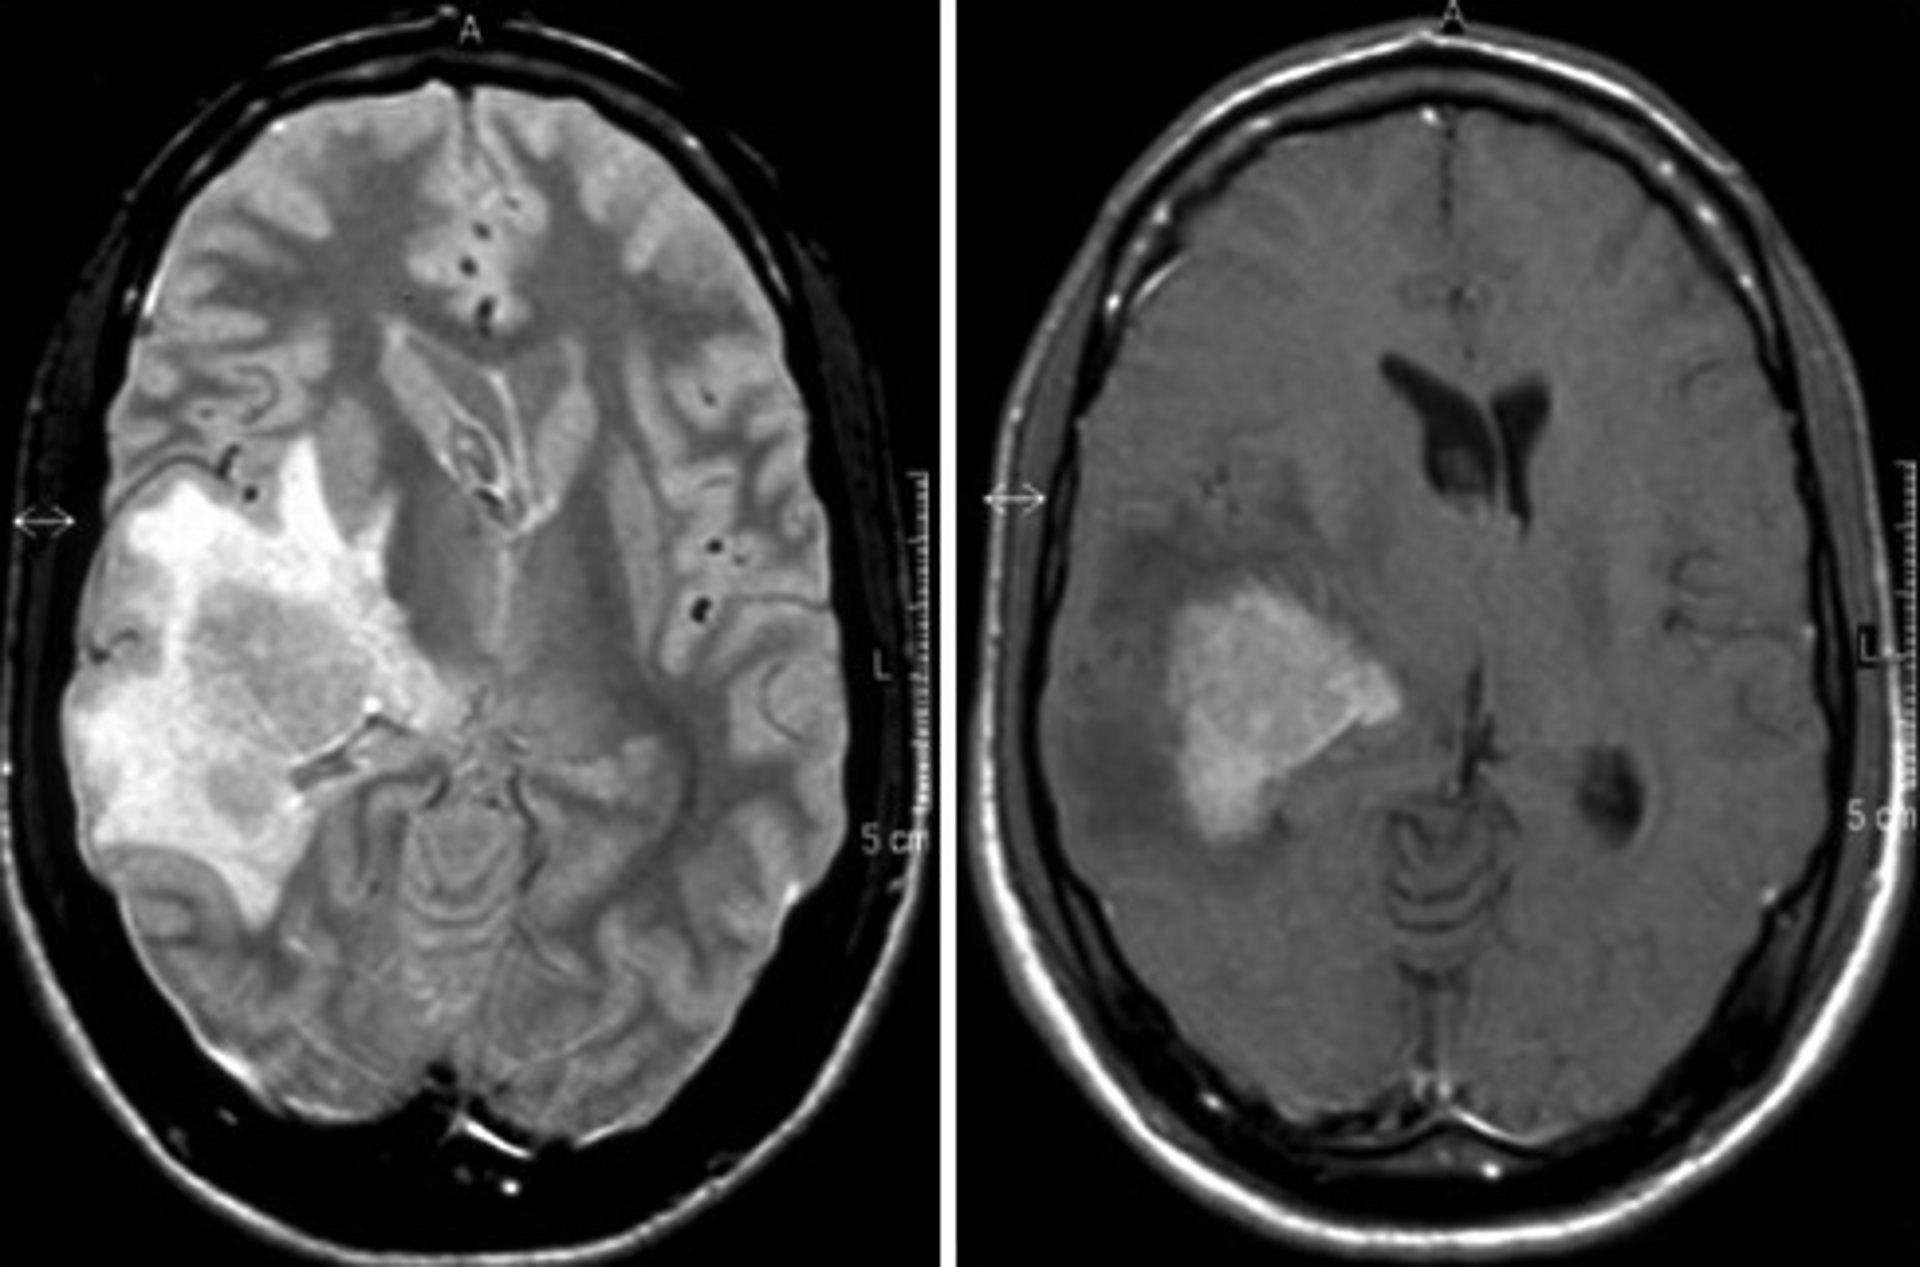

Ahora bien, los hematólogos de este hospital aseguran que el linfoma cerebral se trata de un tumor "raro" debido a su baja incidencia, de modo que "puede resultar difícil la realización de un diagnóstico temprano". Por este motivo, en cuanto aparecen los primeros signos y síntomas, los especialistas realizan pruebas de imagen cerebral, como un escáner y una resonancia magnética.

Además, según explica el doctor Cornago, si se descarta un accidente cerebrovascular y aparece una masa cerebral, "se biopsia dicha lesión. Así, con el resultado histológico, se podrá llegar con certeza al diagnóstico de linfoma cerebral". En ese sentido, destaca que la biopsia es la manera de confirmar que se trata de esa enfermedad y no de otros tumores cerebrales primarios u otras entidades como infecciones.